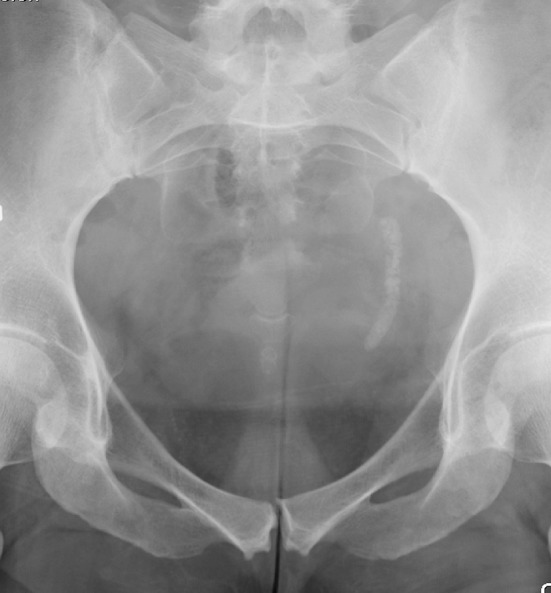

To maintain a non-invasive therapeutic concept, percussion and inversion therapy is an option that should be considered. Several literature reports have shown that such a regimen can be used for improved elimination of residual fragments [116–118]. Not all authors have been successful with inversion therapy [119], and it seems necessary with standardization and improvement of this method to increase the rate of fragment clearance (Fig. 9). The advantage is that many patients treated with inversion therapy can be rendered stone free without invasive procedures. It is possible that elimination of residual fragments in the lower calyces in the future more effectively can be accomplished by ultrasound propulsion [120].

Fig. 9.

Inversion therapy (DIVE). High diuresis is combined with inversion and vibration over the kidney in attempts to move and eliminate fragments